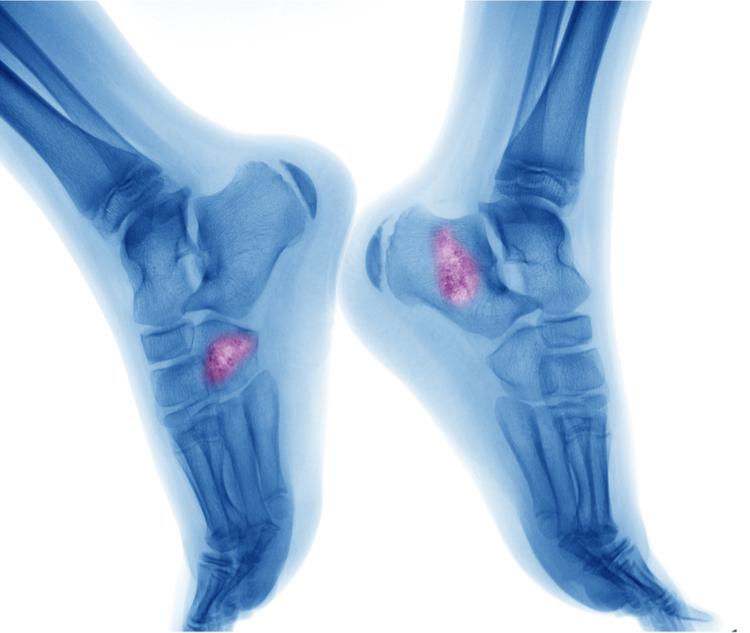

Các xét nghiệm hình ảnh có thể giúp xác định vị trí và kích thước của các khối u xương và cho biết liệu các khối u có lan sang các bộ phận khác của cơ thể hay không. Các loại xét nghiệm hình ảnh được khuyến nghị tùy thuộc vào các dấu hiệu và triệu chứng.

- Chụp X-quang xương